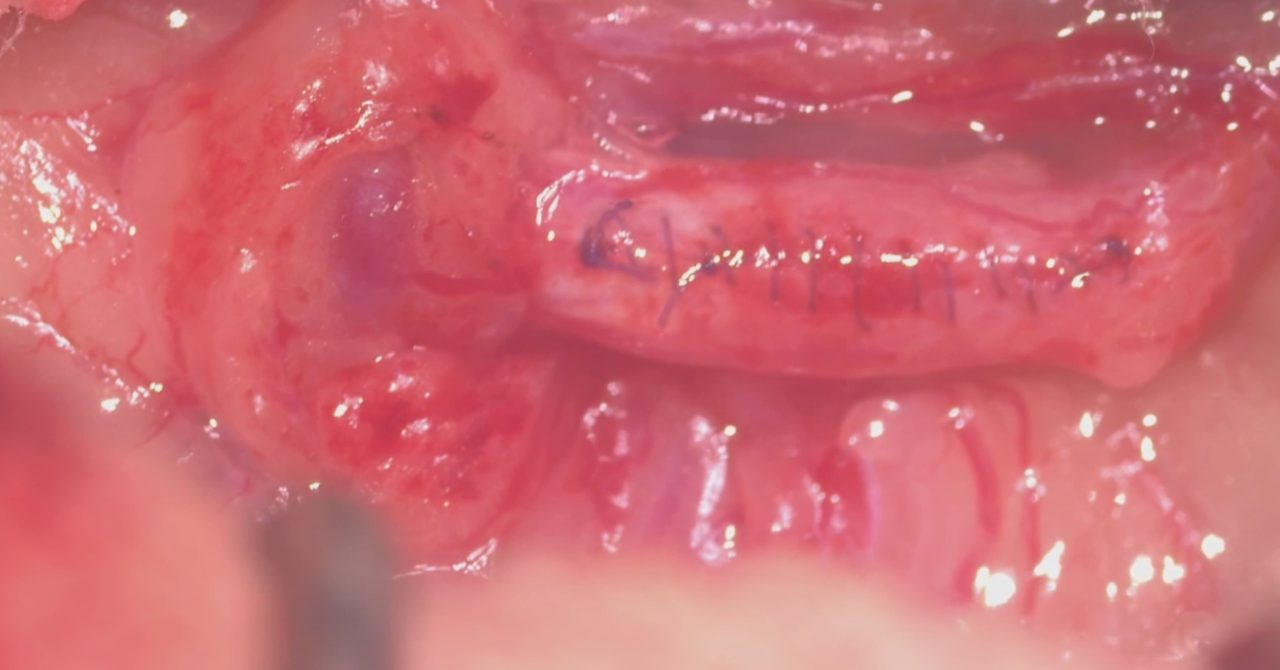

食欲にムラが出てきた。とのことで高齢のワンコがかかりつけ医を受診されました。血液検査で腎数値が軽度上昇していることから腹部のエコーで精査を行ったところ尿管結石が見つかったそうです。”犬の尿管結石”は猫に比べると診断する頻度は少ないのですが、CTで確認すると結石が尿管を閉塞し尿管拡張が確認されました。顕微鏡下で閉塞した結石を除去しました。犬は尿路感染も併発していること多いので尿の培養検査も行います。しばらくは輸液をしながら腎機能のモニターを行います。高齢ですが頑張ってくれました。